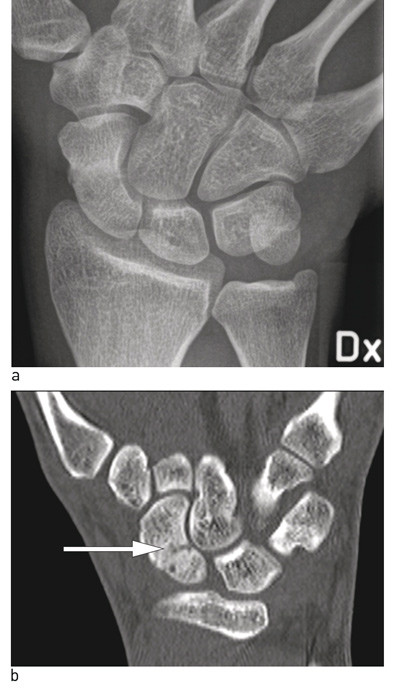

Figure 3  Acute scaphoid fracture, not visible on standard X-ray images. a) Frontal projection, overview picture (difficult…

Figure 3 Acute scaphoid fracture, not visible on standard X-ray images. a) Frontal projection, overview picture (difficult to see fracture lines in scaphoid, b) CT we see fracture line, marked with arrow